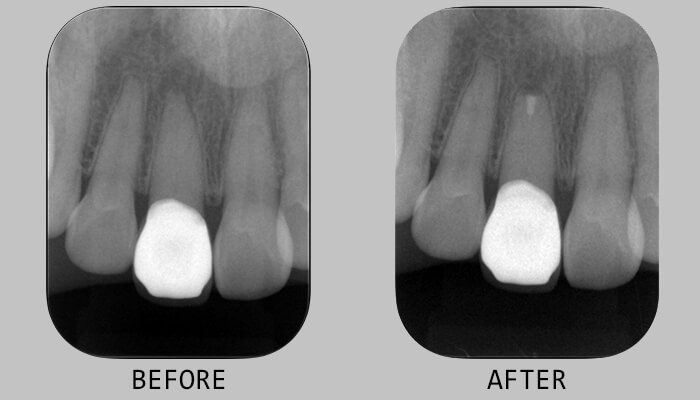

8. 術直後のエックス線検査画像です。

10. 術後半年で、歯根膜腔が明瞭になり、ほぼ治癒と判断できました。

7. 術直後のエックス線検査です。

8. 術直後と術後9ヵ月のエックス線検査の比較です。ほぼ根尖部の透過像は改善しました。

10. 治療前後のレントゲン写真

11. 治療前の写真

12. 治療後の写真

8. 治療前後のレントゲン写真